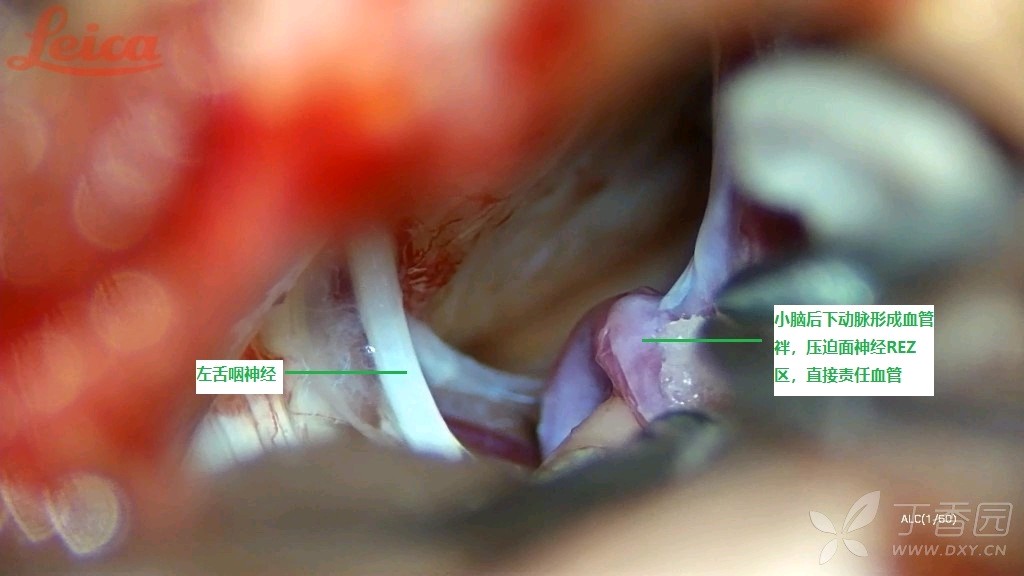

入院完善术前常规检验检查,无明显异常指标及手术禁忌,行左侧面神经MVD手术。关键术程如下:解剖后组颅神经与中组颅神经桥延髓小脑池蛛网膜,首先见小脑后下动脉形成血管袢压迫面神经出入脑干区(REZ),构成直接责任血管(见图2)

图2 小脑后下动脉形成血管袢压迫面神经REZ区